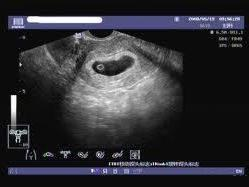

空孕囊是指孕婦在妊娠早期,胚胎發(fā)育異常或停止發(fā)育,導(dǎo)致孕囊內(nèi)沒有胚芽或胎心的情況,對(duì)于期待寶寶的家庭來說,空孕囊的出現(xiàn)無疑是一種打擊,了解空孕囊的征兆,早期識(shí)別并采取措施,對(duì)保障母嬰健康具有重要意義,本文將為您詳細(xì)解析空孕囊的十個(gè)征兆,以便您及時(shí)察覺并處理。

通過B超檢查發(fā)現(xiàn)胚胎未按照正常時(shí)間發(fā)育,如未按時(shí)出現(xiàn)胚芽、胎心等,可能是空孕囊的表現(xiàn)。

10、羊水過少或無羊水